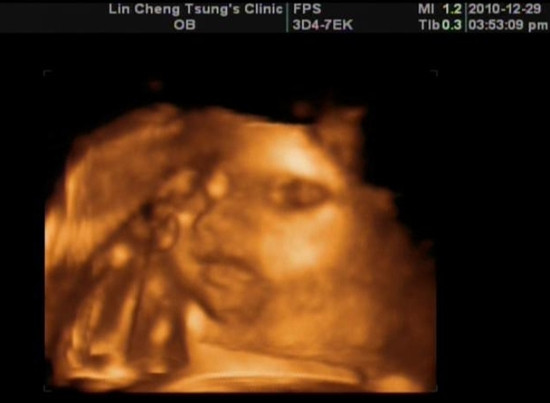

2010.12.29 27W+5D

有別於2D超音波只提供平面的影像...比較難想像寶寶在肚子裡的樣子

4D超音波利用電腦處理影像的技術...可以看到每秒5~25張的連續立體影像

也就可以看到寶寶在肚子裡活動的情形...除了照片外...也會提供DVD供收藏

通常會建議在28週做...寶寶太大很容易東擋西擋...就很難看到全貌了

為了給寶寶一個紀念...我們也預約了照4D的時間...

在路上還一直叫寶寶起床...別讓媽咪看不到你嘿!

果然~下午是林小兔的睡覺時間...硬是被醫生伯伯吵醒

不甘願的睜開一隻眼睛給我們看

手手也肥嘟嘟的~

照4D真的挺好玩的...比平常照的高層次真的清楚很多

喝羊水...伸懶腰...翻來翻去...在肚子裡可忙的呢!